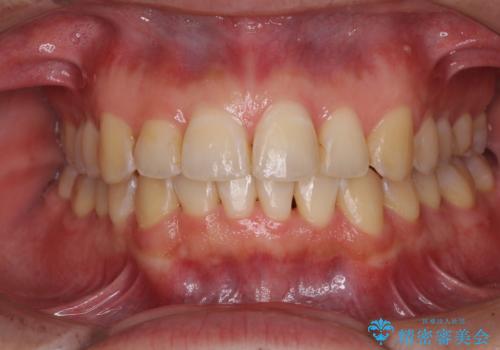

- 八重歯と乳歯が残っていることを気にして来院された患者様です。

乳歯が3歯残っており、下顎は左右ともに後続永久歯がない状態でした。

口元が突出しており、口が閉じにくかったため、乳歯を含め上下5歯を抜歯して矯正治療を行うこととしました。

下顎の乳歯は永久歯と比べて幅が大きいため、抜歯した場合のスペースが大きく、治療には長期間を要することが一般的です。

今回の患者様は中学生ということもあり、成人の患者様と比べ動きが速く、2年間で治療を終えることができました。